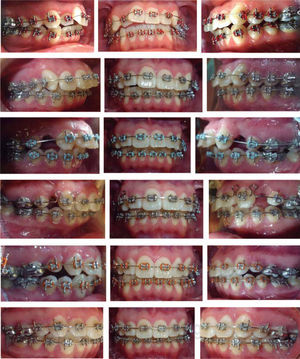

Secuencia de tratamientoDe acuerdo con la técnica se colocó aparatología ortodóntica prescripción Roth calibre .022“x .028”, como anclaje se indica la utilización de barra transpalatal, seguido de las extracciones. Siguiendo las indicaciones de la técnica, se llevó a cabo la fase I de nivelación con arcos de níquel-titanio redondos. Posteriormente se colocaron arcos DKHL para la fase II de cierre de espacios. Durante la fase III se colocaron arcos rectangulares para la torsión e inclinación finales, que se obtuvieron a través de la prescripción. El asentamiento oclusal se logró utilizando elásticos cortos.

En este caso clínico el paciente fue tratado de acuerdo con la filosofía y técnica de Roth, con extracciones únicamente de primeros premolares superiores, por no presentar discrepancias dentoesqueletales significativas, ni apiñamiento severo del arco mandibular, coincidiendo con lo propuesto por Strang 1957 y Bishara 1995.3,4

Fue necesaria la implementación de las dobles barras transpalatinas para apoyar la retracción del segmento anterior; sin embargo, a pesar de obtener resultados aceptables, se presentó pérdida de anclaje posterior que limitó la retracción completa del segmento anterior y la consecuente mesialización de los primeros molares superiores, a pesar de mantener durante toda la fase I y II del tratamiento las dobles barras transpalatinas; esto se debe a la mecánica de deslizamiento normal de los segmentos anteriores y posteriores, según lo reportado por Sichuan en el 2011. Existe una relación de movimiento de los dientes maxilares anteriores con los posteriores de 1:1.3, es decir, se produce más mesialización que retracción.12

Lo anterior hubiera justificado la utilización de miniimplantes vestibulares para lograr toda la retracción necesaria y evitar la mesialización del segmento posterior, dado que existen estudios que sustentan la ventaja del uso de estos aditamentos como máximo anclaje.13